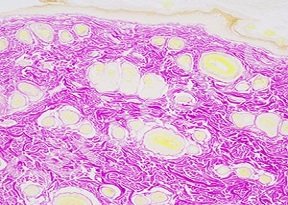

实验结果展示:

胶原纤维呈红色,其他组织成分呈黄色。